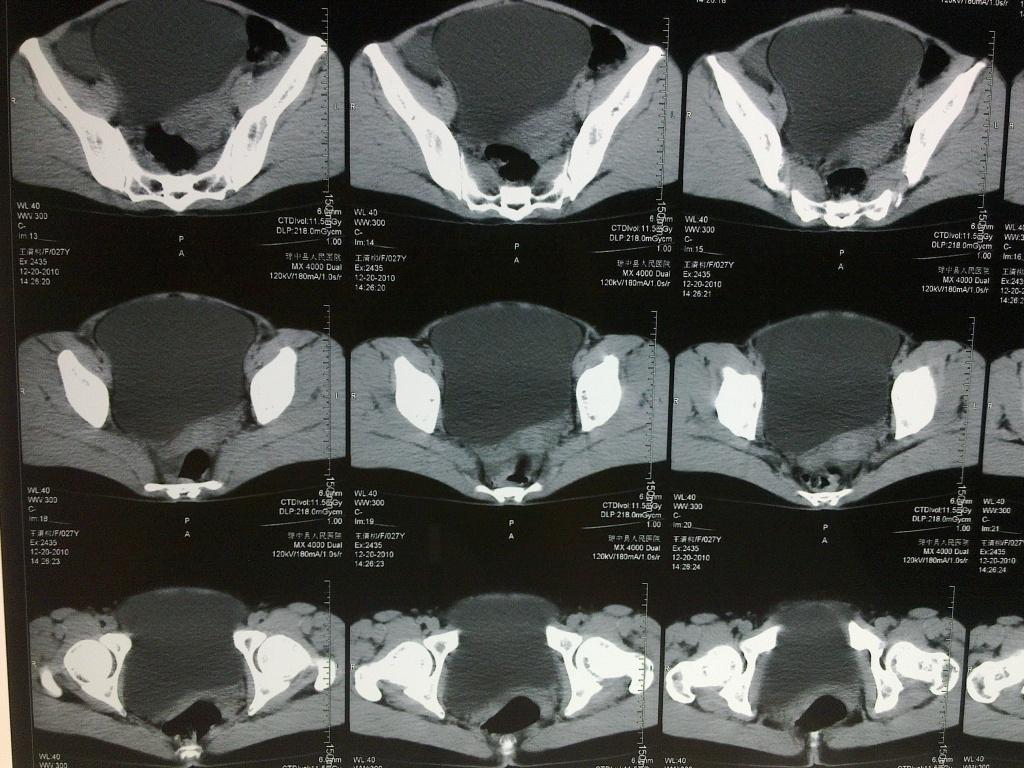

【讨论】盆腔包块,请问诊断是什么?

图片尺寸2816x2112